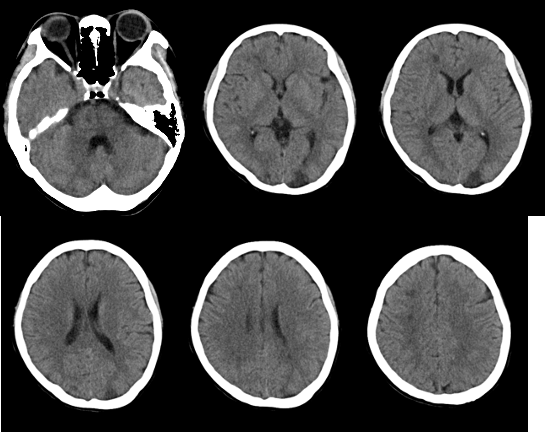

↑ 头颅 CT:右额叶、右侧半卵圆中心、左侧枕叶新出现多发斑片状低密度影,转移瘤可能性大。

1. 本病例影像学表现提示的诊断线索:青年女性,脑内新见散在多发病灶,散在分布于多个脑动脉供血区,包括幕上幕下,皮层及深部白质,无明显占位效应,病灶周围无水肿,弥散受限,增强扫描左枕叶较大病灶不均匀强化,余病灶无明显强化。

定性诊断:本病例特点为青年女性,有明确肺癌病史,无明确神经系统症状,CT 发现颅内新发多发病灶,结合病史首先不除外转移瘤,MR 进一步检查病灶符合多发急性期脑梗死,确诊脑梗死不难,难的是确认脑梗死的发病原因。